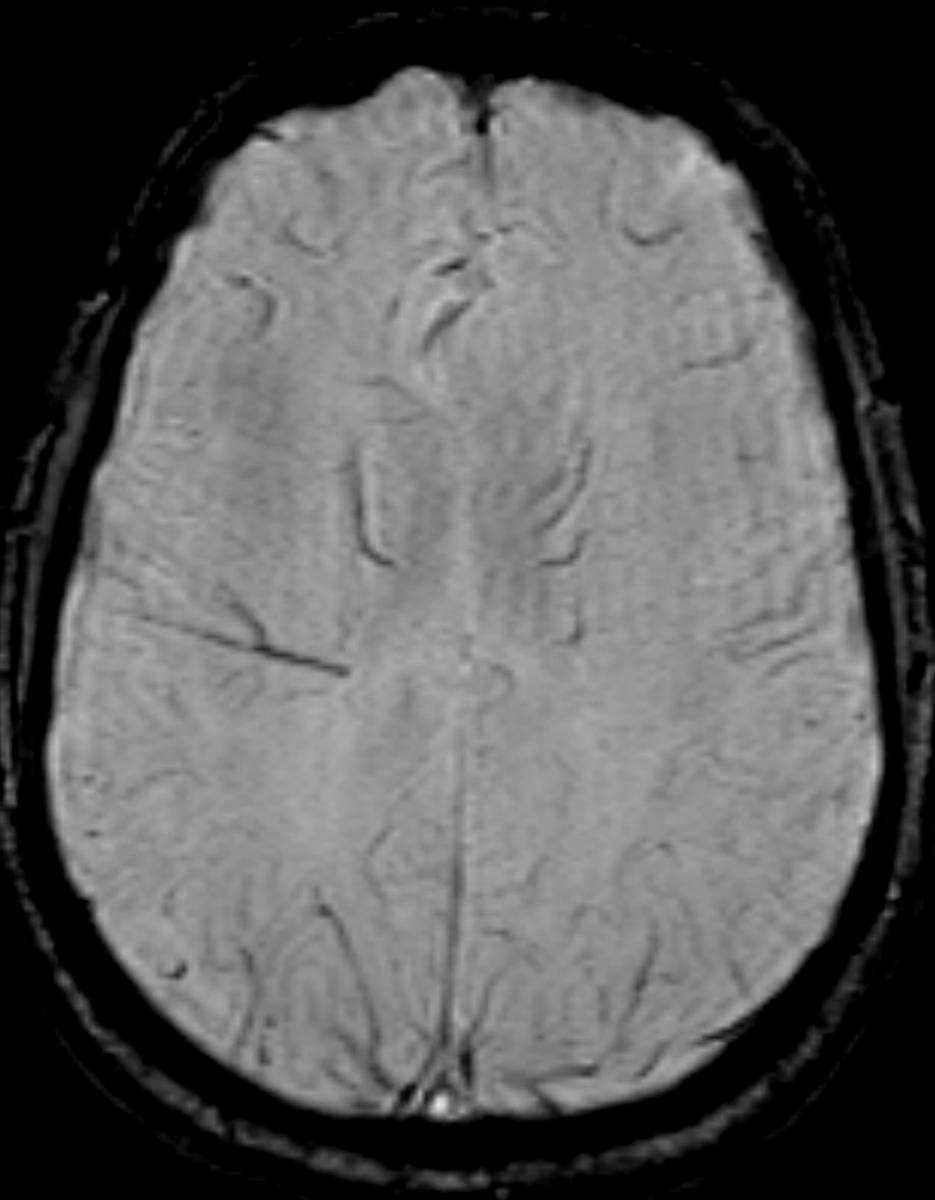

This is a case of Langerhans Cell Histiocytosis, or LCH, of the pituitary gland and infundibulum in a 6-year-old male. The first image is sagittal T1-weighted with some motion degradation. There is thickening of the infundibulum and pituitary gland itself, with classic loss of the typically hyerintense posterior pituitary. The second image is a noncontrast coronal T1 correlate redemonstrating infundibular thickening as well as enlargement of the pituitary gland itself. The third image is with T2 weighting in the coronal plane redemonstrating thickening of the pituitary stalk. The fourth through sixth images are multi planar postcontrast T1-weighted sequences demonstrating avid post contrast enhancement of the markedly enlarged infundibulum and pituitary gland itself. LCH is a reactive clonal disease of the monocyte-macrophage system, and may affect almost any organ system. LCH CNS involvement may fall into one of several forms such as: osseous lesions with or without soft tissue components, intra-cranial extra-axial lesions, such as in the hypothalamic-pituitary region, meninges, or circumventricular organs, intracranial intra-axial lesions and cerebral atrophy. Langerhans cell histiocytosis is the most common cause of infundibular thickening in childhood. Diabetes insipidus is the typical clinical presentation of hypothalamic-pituitary involvement.